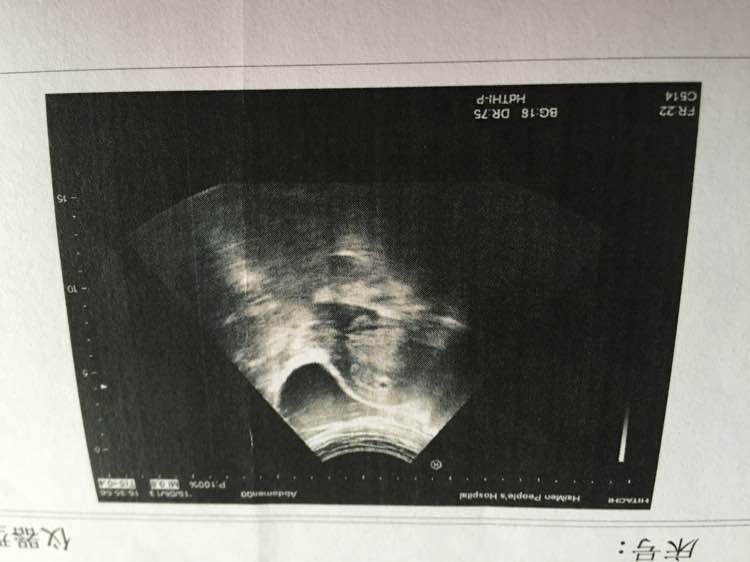

这是第四四周去拍的彩超 医生说还得拍 看不清在宫内还是宫外 有懂的亲吗 能告诉我在宫内还是宫外吗